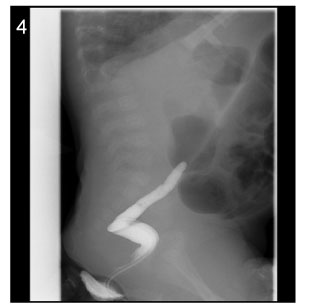

Fig. 4

Image of barium enema at the age of 43days (Case No. 4).

The contrast cannot advance further.